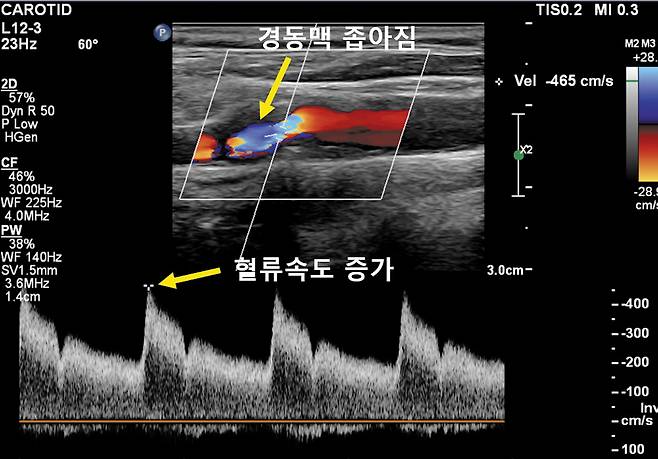

경동맥 초음파 검사는 어떻게 구성되나?

크게 두 가지를 본다. 혈관 벽 3층의 막 중 내막·중간막 두께 측정과 내경동맥 등 혈류 속도 측정이다. 두께는 0.1㎜ 단위로 세밀하게 측정하기 때문에 검사자에 따라 경동맥 협착을 과소 측정하거나 동맥경화반(플라크)을 놓치기 쉽다. 또 내경동맥 혈류 속도가 매우 빠르다고 해서 꼭 심한 협착이 있는 건 아니다. 내경동맥이 꼬불꼬불해 정상 혈관이 꺾어지는 부위에서 혈류 속도가 빨라질 수 있기 때문이다. 검사 기기뿐 아니라 작은 차이를 잡아내는 전문가의 숙련도가 중요한 이유다. 고해상도 MRA, 혈관 조영술도 감별 진단에 도움이 된다.

검사상 협착의 이상 정도는 크게 3단계다. 1단계는 내막·중간막의 최대 두께가 1.1~1.4㎜로 경미한 수준이다. 고지혈증 등 원인 질환을 치료·관리하며 1년 간격의 주기적인 추적 검사로 경과를 관찰한다. 2단계는 두께가 1.5㎜이상인 초·중기 단계로 동맥경화반(플라크)이 생길 때다. 환자 개개인에 맞춰 처방약(항혈소판제, 스타틴)을 복용하거나 주기적 검사로 지켜본다. 3단계는 두께 5㎜이상(70%이상) 혹은 혈류 속도가 1초당 200㎝ 이상인 심한 협착 단계로 약 복용 혹은 시술·수술을 고려한다. 환자의 적극적인 치료 의지와 복약 순응도가 중요하다.